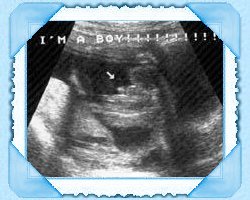

Due to a lot of stress when Lonelywolf left to fight for our country our

baby was not moving and it had me worried.

I went to the doctor and they did another ultrasond on me.

This is when i got the wav of the babies heart beat so Wolf could hear.

IT'S A BOY!!!!!